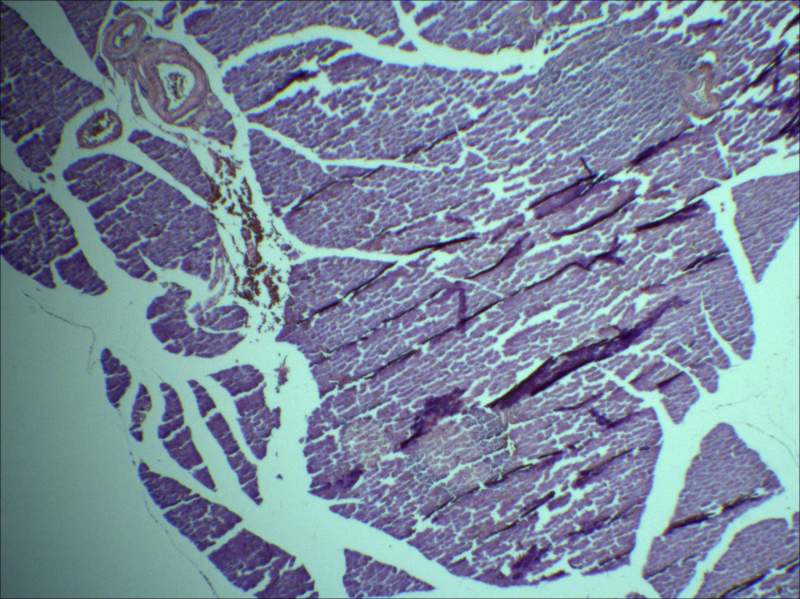

我最近自己做的胰腺的HE 染色,效果一直很不好,求大神指教:如何才能做出一张文献中那么漂亮的图,最好能给我一个做胰腺的protocol。 如果效果好 再补100个金币 我切得胰腺好像切碎了 细胞之间没那么致密所有组别的胰腺都很松散。 用的是多聚甲醛过夜固定的,刀片也经常换。 pancreas L2P.jpg |